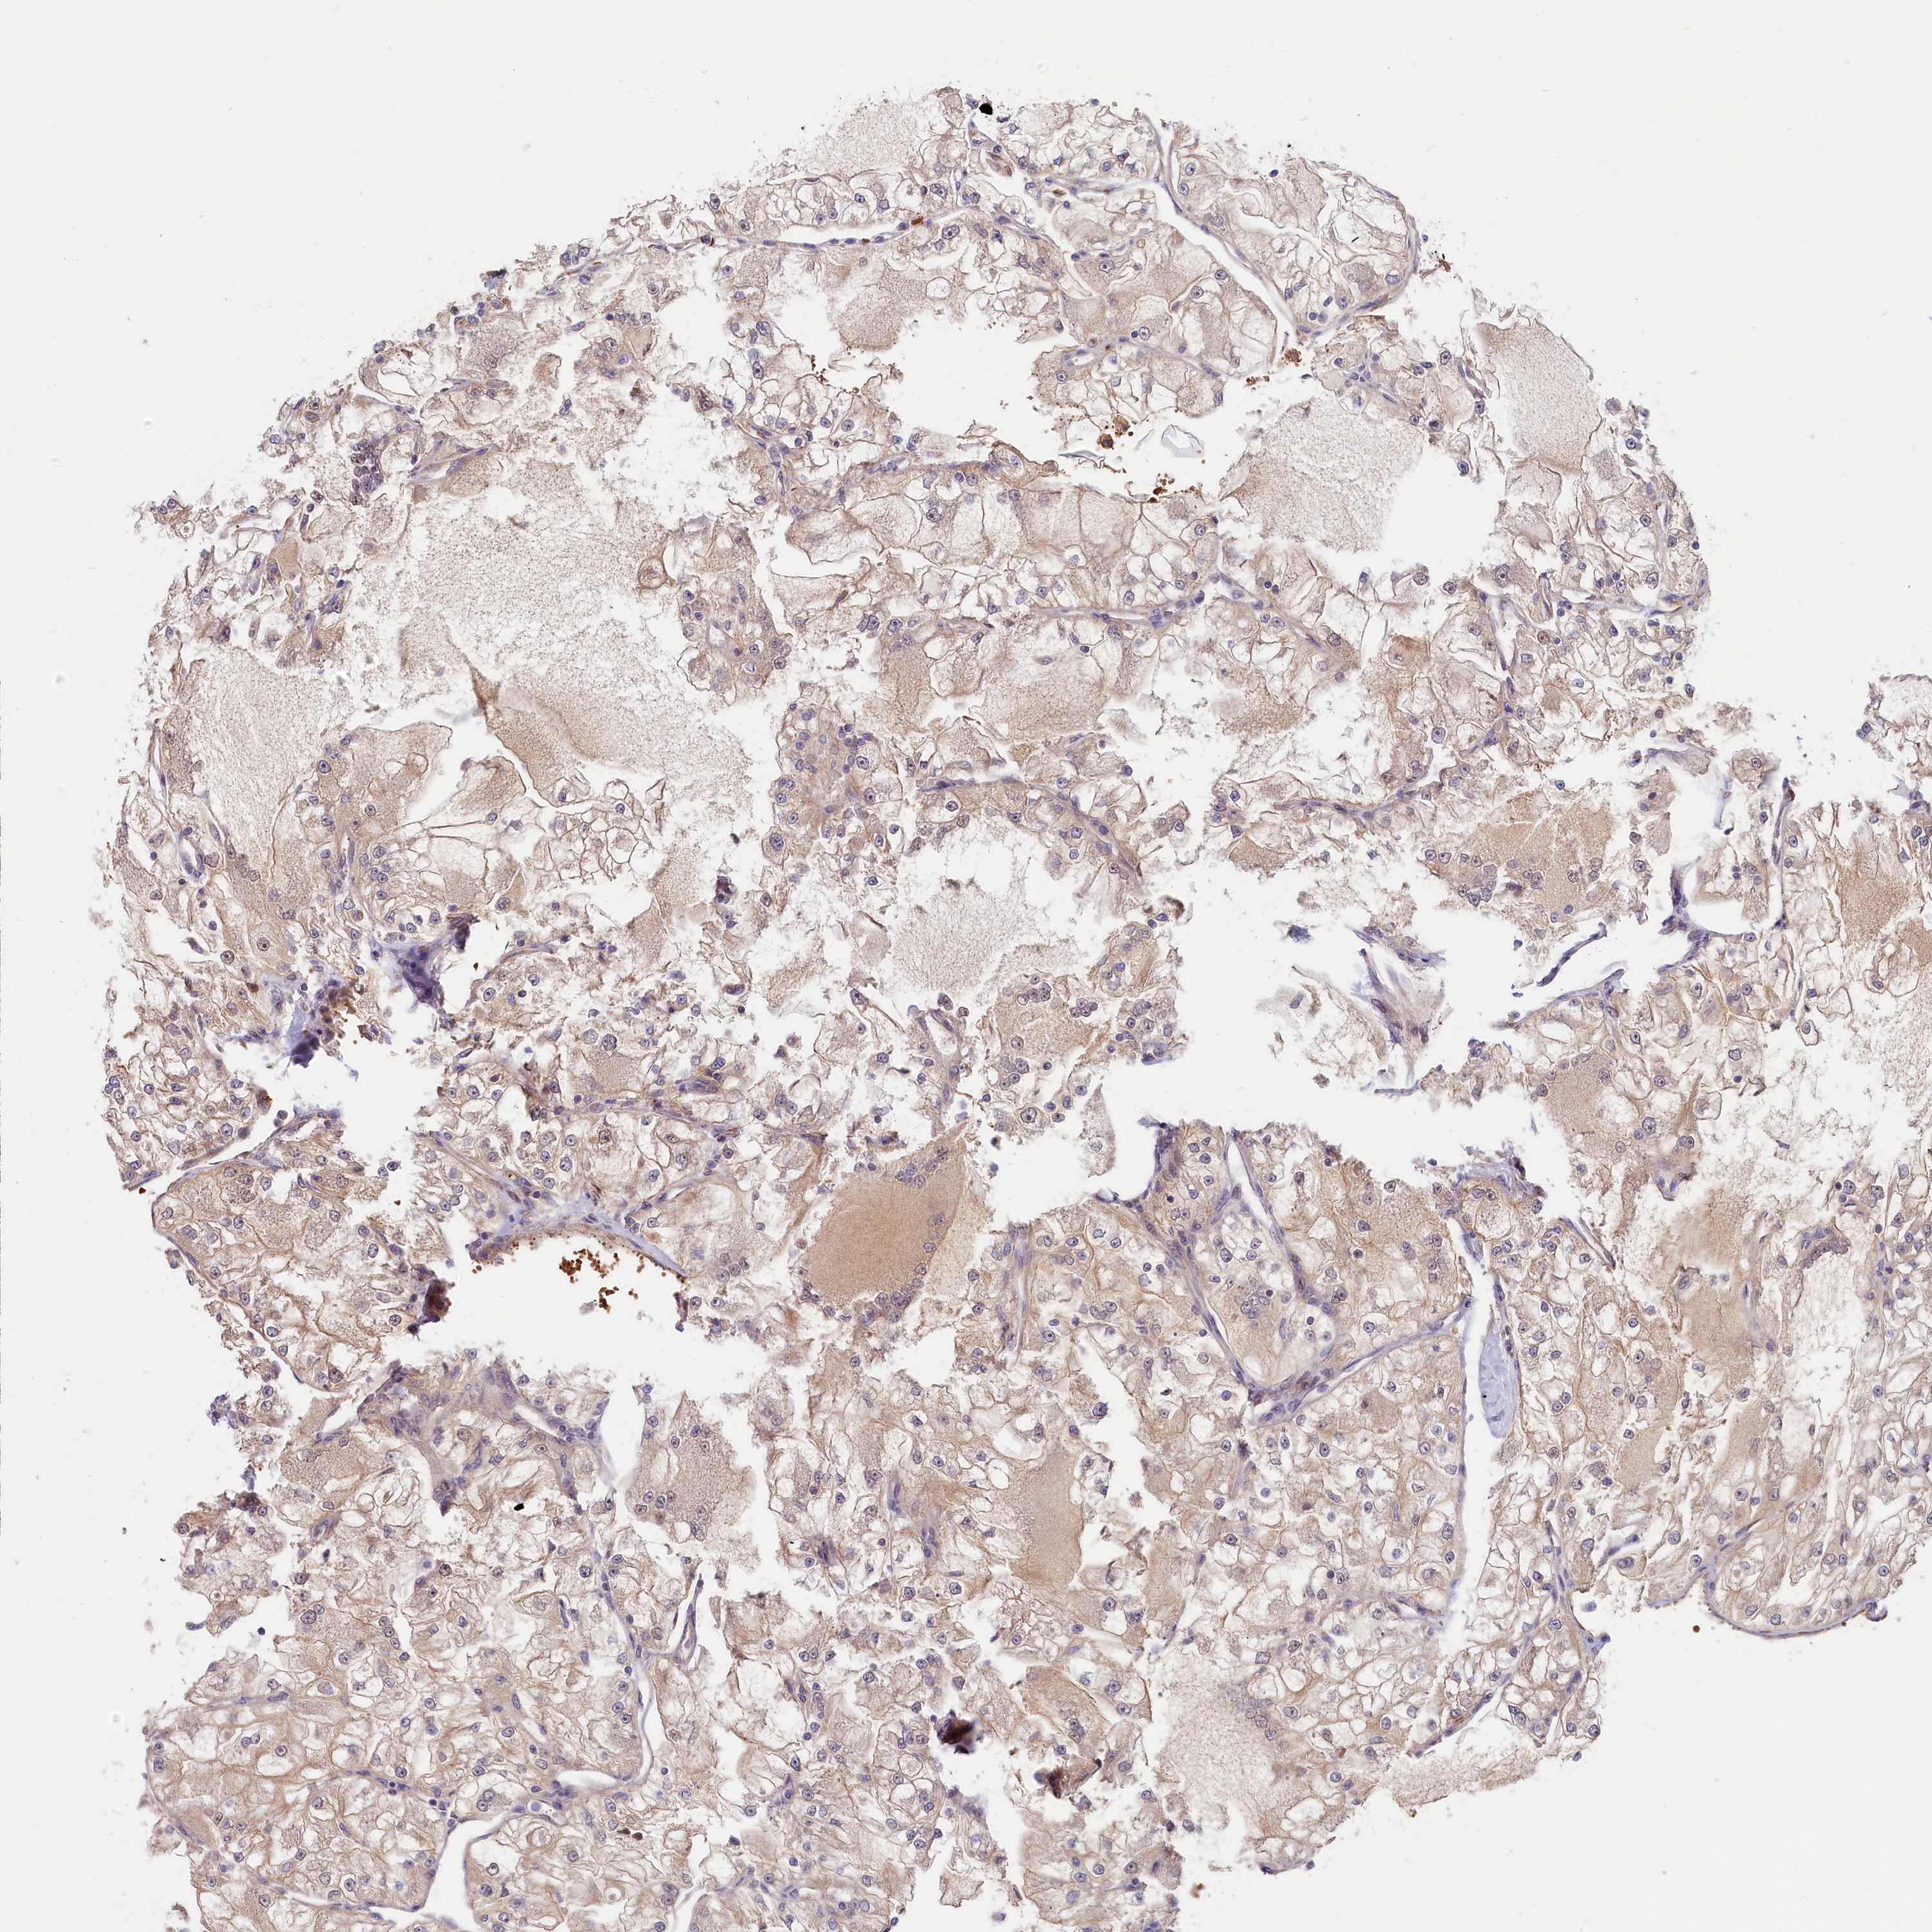

CANCER RENAL CANCER Show tissue menu

KICH TCGA KIRC TCGA KIRC VALIDATION KIRP TCGA PROTEIN RCC CPTAC PROTEIN EXPRESSION